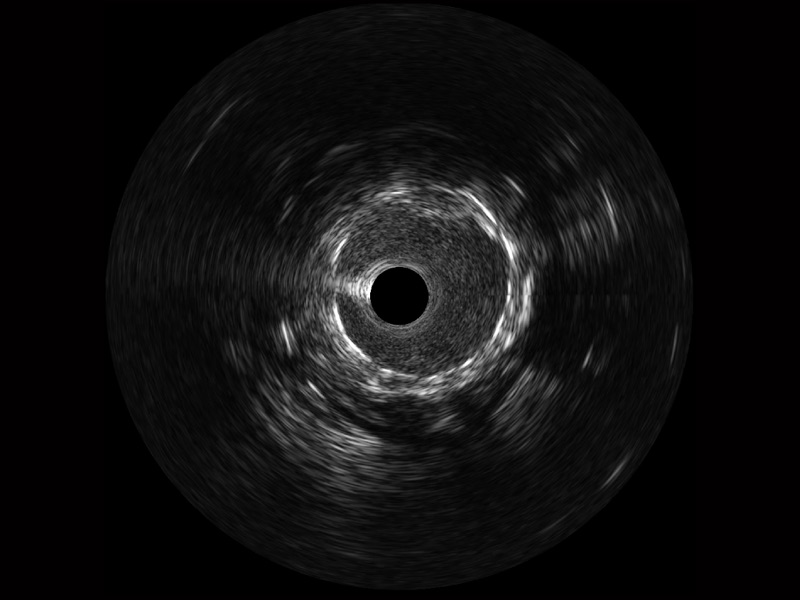

竞技宝(JJB)官方网站宽频IVUS图像

传统IVUS图像

对比传统IVUS导管成像,竞技宝(JJB)官方网站宽频IVUS图像的近场支架梁显影更细腻,远场中膜外血管仍清晰可辨,兼顾远中近,兼顾分辨力与穿透深度